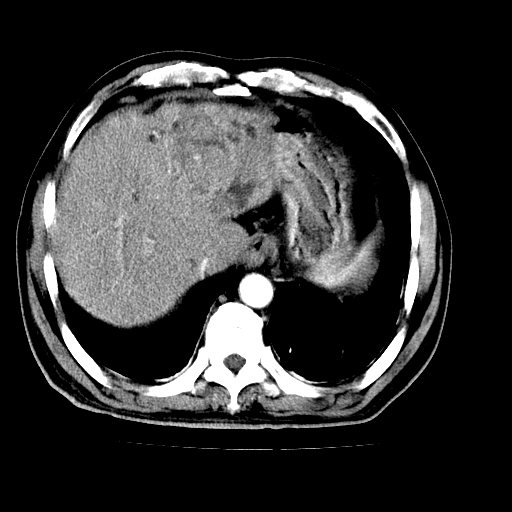

男,66岁,上腹部不适、黄染一周。彩超示:肝左叶占位,肝内胆管扩张,胆总管扩张,胆总管占位?

肝左叶不规则软组织肿块影,边缘不规整邻近肝实质受累分界不清;肝内胆管(左叶)明显扩张成“软藤状”,诊断:肝左叶胆管细胞癌。

支持肝左叶肝内胆管细胞癌伴胆总管及门脉左支受侵。

肝左叶不规则软组织肿块影,边缘不规整邻近肝实质受累分界不清;肝内胆管(左叶)明显扩张成“软藤状”,诊断:肝左叶胆管细胞癌。胆囊钙乳症。